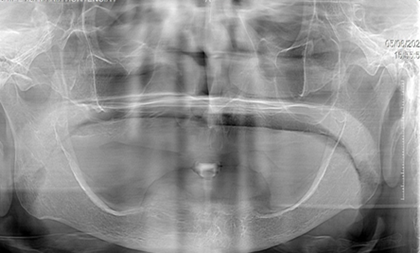

EXAMEN RADIOGRÁFICO

Paciente presenta elevaciones irregulares en el maxilar inferior (Figura 2).

Figura 2. Radiografía del maxilar inferior.

Elaboración: Los autores.